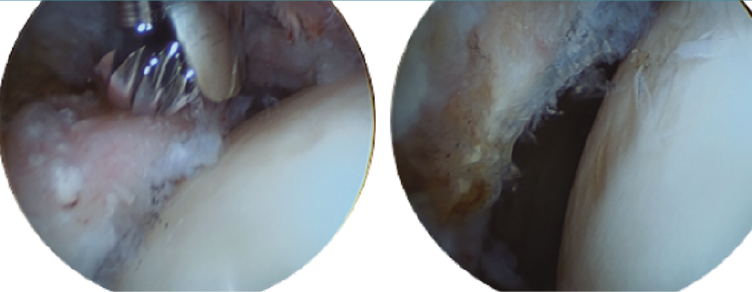

Retiraremos los osteofitos con una fresa desde la unión capsulolabral para movernos más cómodos y seguiremos con la resección del os labrale, osteofito o labrum calcificado (Figura 3).

Figura 3. Paciente con osteofito en el reborde acetabular (imagen izquierda). Resección del osteofito en el reborde acetabular (imagen derecha).

Tras el paso anterior, aplicaremos tracción para reinsertar el labrum y tratar las posibles lesiones con técnicas de estimulación medular, terapias celulares u otros productos biológicos (Orthokine®, CarGel® o plasma). Para esto, nos podemos ayudar de los punzones habituales manuales o los nuevos dispositivos motorizados (PowerPick®, MicroDrill®).